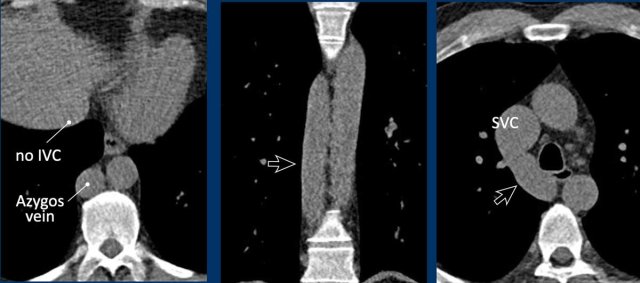

Azygos continuation of the inferior vena cava

In this variant there is absence of the infrahepatic portion of the IVC with the infrarenal and renal segments draining via an enlarged azygos vein into the superior caval vein.

The supra-hepatic segment of the IVC is present but drains only blood from the hepatic veins into the right atrium.

Azygos continuation of the inferior caval vein is normally an incidental finding in asymptomatic patients, although it might be associated with other cardiovascular abnormalities, as well as with splenic absence or polysplenia.

The importance of not overlooking this condition lies mainly in its relevance for surgical planning as well as endovascular procedures, as it prevents catheterizing the right heart from inferior.

Azygos continuation of the IVC showing the characteristic ‘double aorta’ configuration at the level of the diaphragmatic crus, and dilatation of the azygos vein all the way towards the connection to the SVC.